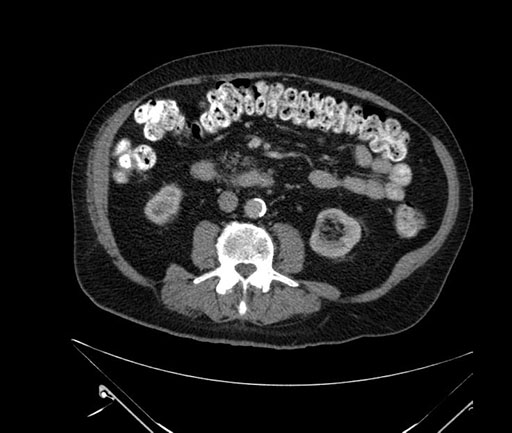

Imaging Analysis

Look through the patient's CT scan to identify any areas of concern for the necessary procedure.

Based on your CT findings, which issue(s) would give reason for "planned slowing down moment(s)" in this case?

Considering a standard Whipple procedure, what step(s) of the operation would you do differently in this case?